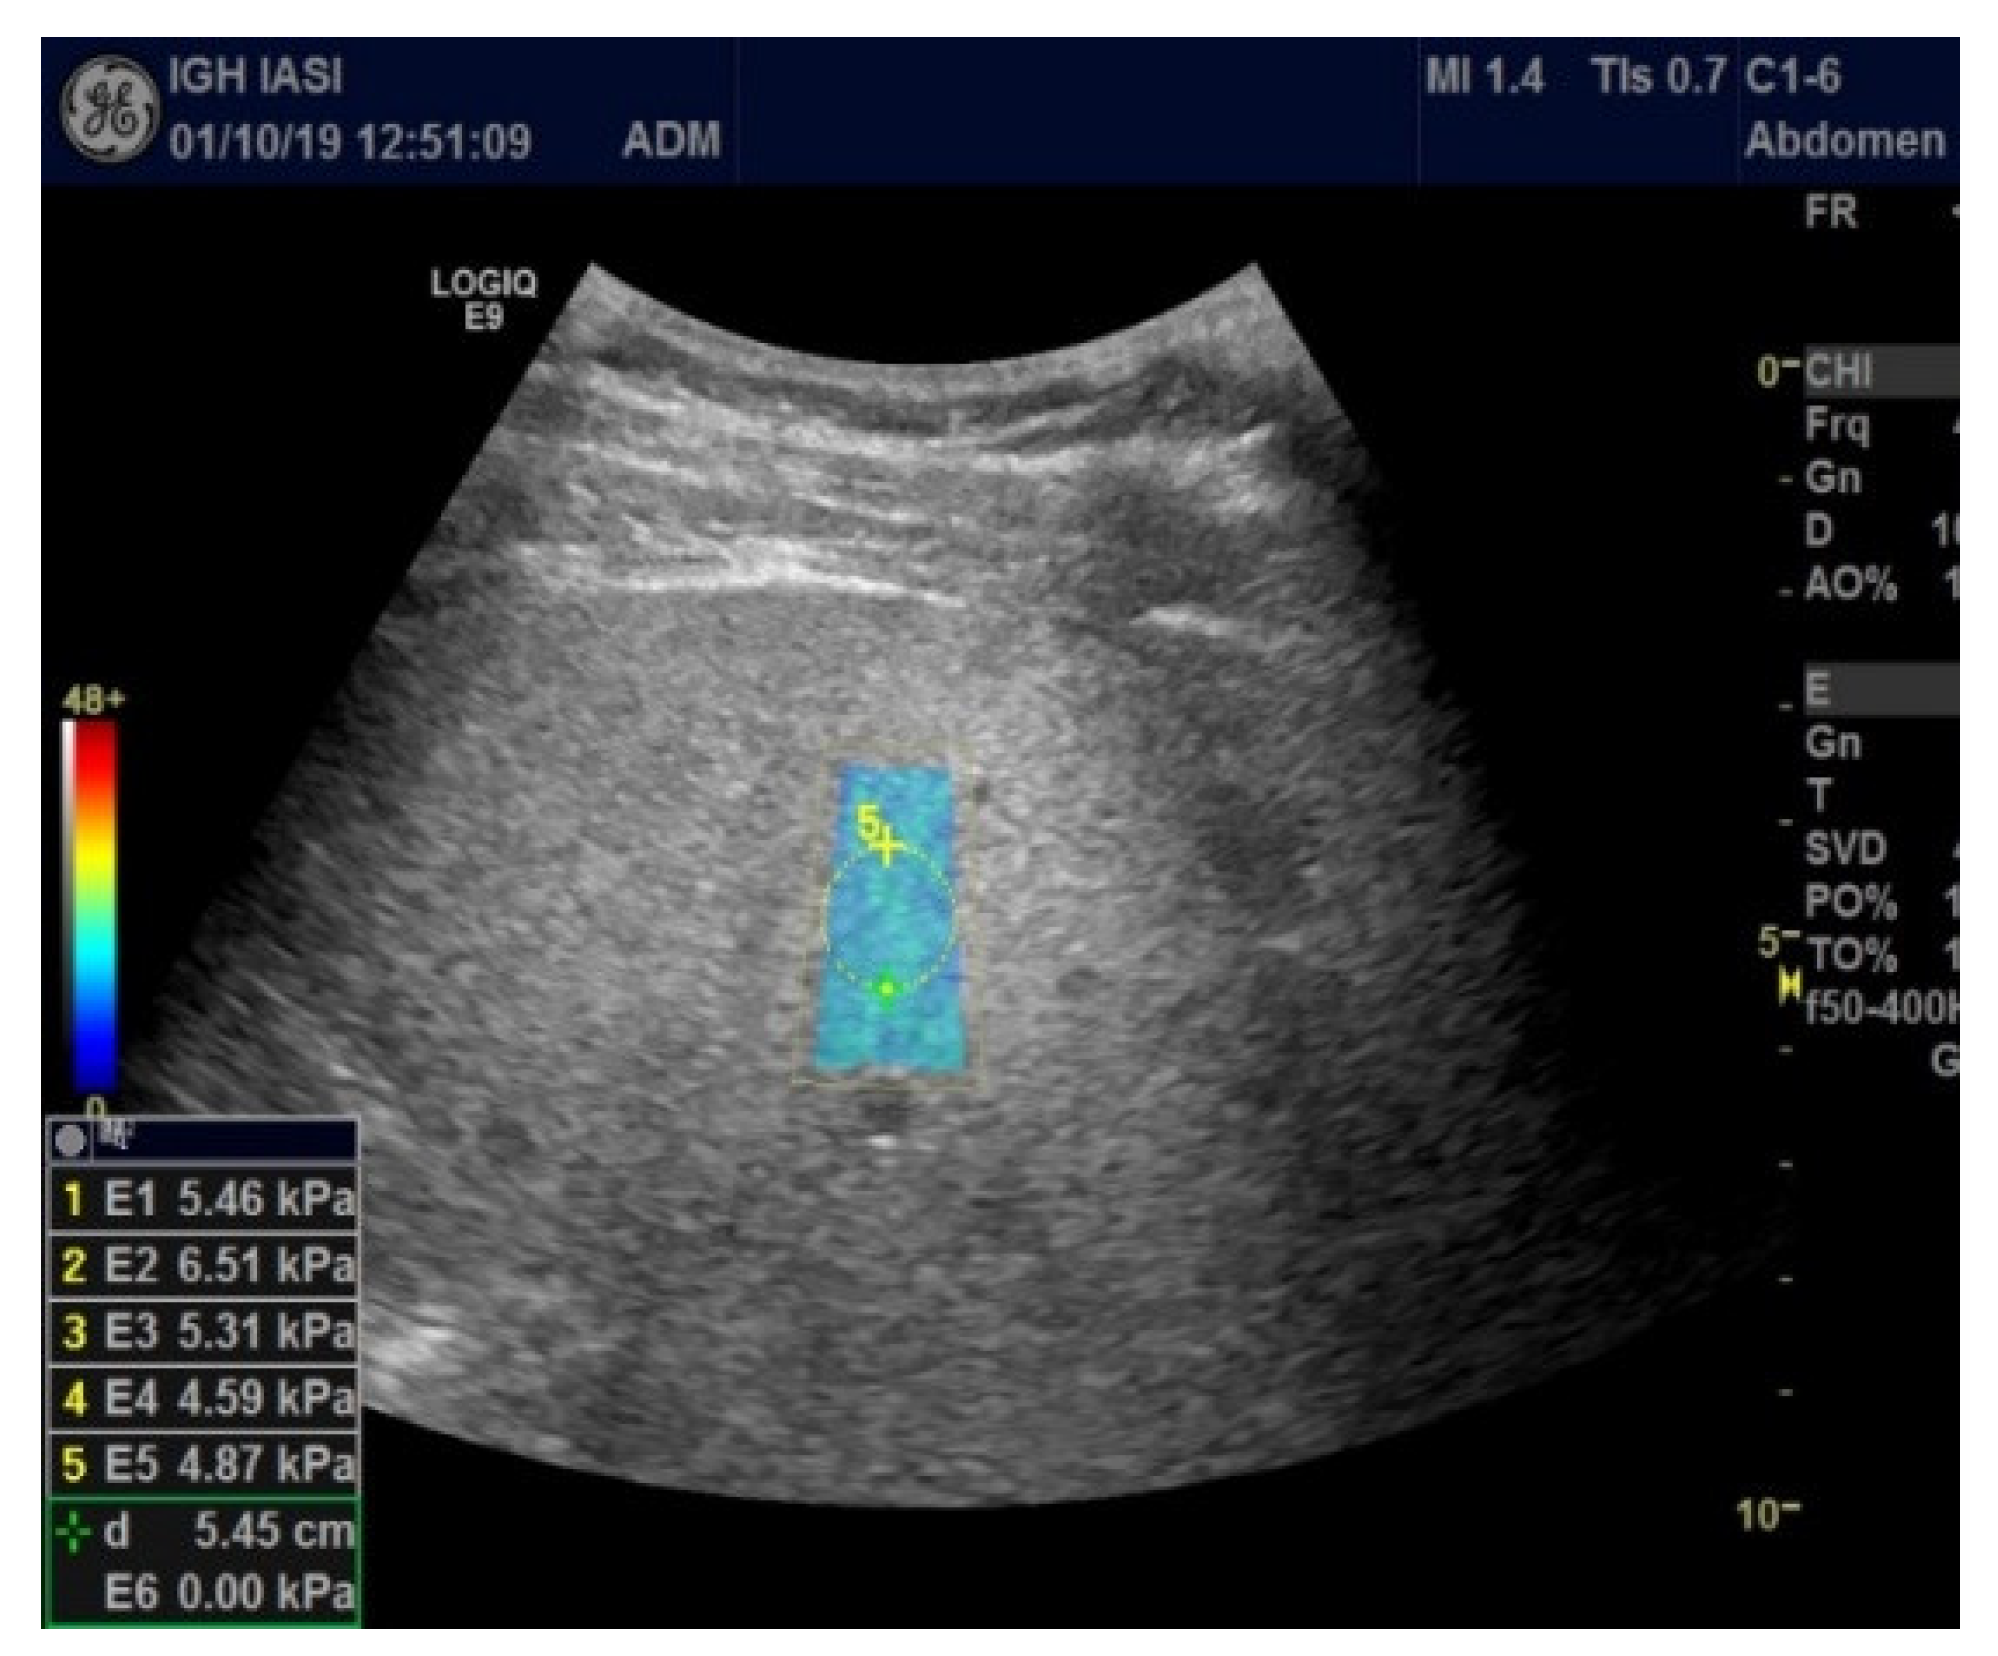

2. Materials and Methods

Study Protocol